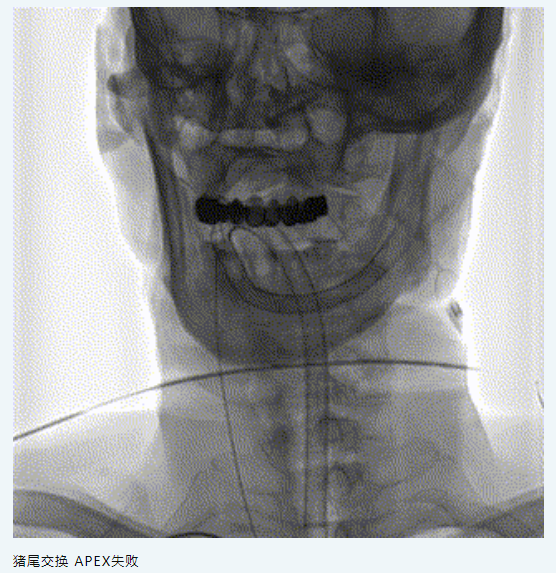

五、治療中影像

image.png

6.7F APEX TRA SYSTEM橈系統(tǒng):1、外徑細(2.32mm),對橈動脈侵擾小,內(nèi)腔大(0.081”):可兼容5F中間導管高到位;經(jīng)橈專用,弓部支撐性較長鞘、導引導管、中間導管、DA更強;APEX橈系統(tǒng)配套有130/140cm長SIM2,長SIM2管同軸治療可避免交換失敗,使顱內(nèi)病變更加便捷。